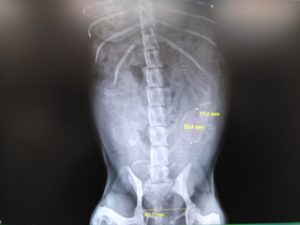

レントゲン検査

3頭の胎児を確認出来ました(・∀・)